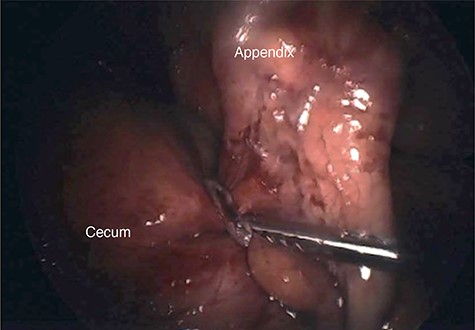

There was concern that the patient was not mounting an appropriate response to infection due to her history of immunomodulator use. Therefore, it was decided to take the patient to the operating room for a diagnostic laparoscopy with likely appendectomy. Once in the abdomen, an edematous and ischemic-appearing appendix was visualized in the right lower quadrant. There was a thick adhesive band noted to be compressing the base of the appendix (Fig. 2). This band was connected to scar tissue along the left ovary and fallopian tube. An ultrasonic energy device was used to take down the adhesive band in its entirety. An appendectomy was also performed.

Intraoperative photograph of a thick adhesive band noted to be compressing the base of the appendix.